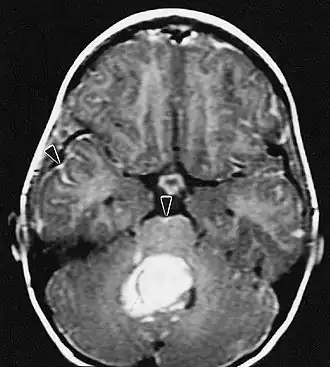

Medulloblastoom

Het medulloblastoom is een zeer kwaadaardige tumor van het centrale zenuwstelsel. Deze wordt gevormd uit zeer primitieve zenuwcellen en bevindt zich altijd in het gebied van de kleine hersenen, zit in de buurt van de hersenstam medulla oblongata. De tumor zaait dikwijls uit binnen het centrale zenuwstelsel. De prognose hangt af van veel factoren. Jonge kinderen en patiƫnten met uitzaaiingen hebben een slechte prognose. De behandeling hangt af van de leeftijd en de uitbreiding van de ziekte. Patiƫnten met een leeftijd boven de 5 jaar, die geen uitzaaiingen hebben en waarbij de tumor geheel of vrijwel geheel operatief verwijderd is worden behandeld volgens een protocol van de SIOP. Er wordt gestart met bestraling van het gehele centrale zenuwstelsel en aansluitend wordt gedurende ongeveer een jaar chemotherapie gegeven. In deze gevallen is de kans op overleving ongeveer 75 %.